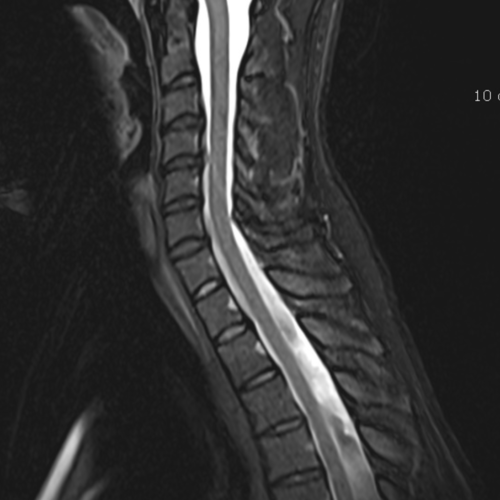

Cet examen est réalisé pour analyser les différentes structures anatomiques du rachis cervical : disque, articulaire postérieure, sac dural, moëlle épinière, nerf C3C4C5C6C7.

Cette examen permets de diagnostiquer:

- les hernies discales

- les conflits disco-radiculaires

- un canal cervical rétréci

- la myélopathie cervico-arthrosique

- l’arthrose articulaire postérieure

- les rétrécissements de foramens

- les tassements vertébraux

- la disco-uncarthrose